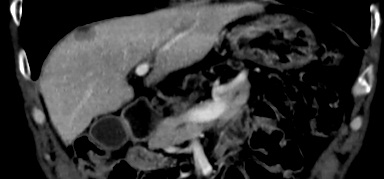

09-01行“奥沙利铂+替吉奥”化疗1周期,10-03至11-25行“曲妥珠单抗+奥沙利铂+替吉奥”治疗3周期。10-24复查胸腹部CT扫描:多处病灶均缩小,CEA、CA199均下降,评估SD缩小,体重增加5%,营养状况改善,PG-SGA评级为B级。

一线治疗有效